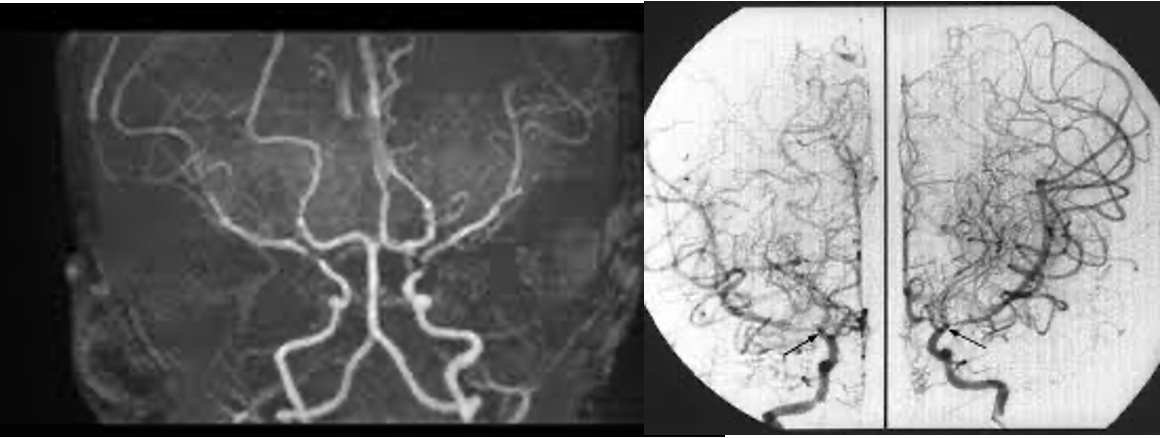

• 정의: distal int. carotid artery나 proxima MCA/ACA 가 점차 좁아지거나 막히면서 작은 collateral vessel들이 형성되는 질환

• MRA, 뇌동맥 조영술 → “puff of smoke” appearance